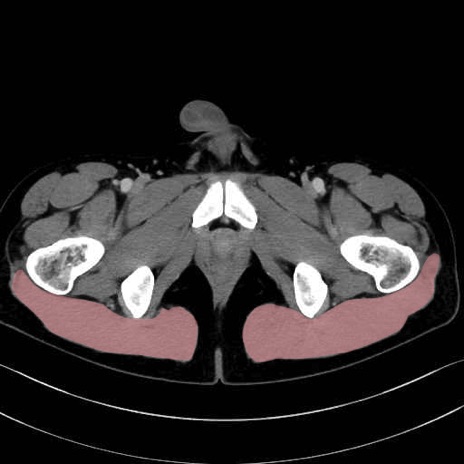

大殿筋 (Gluteus maximus)